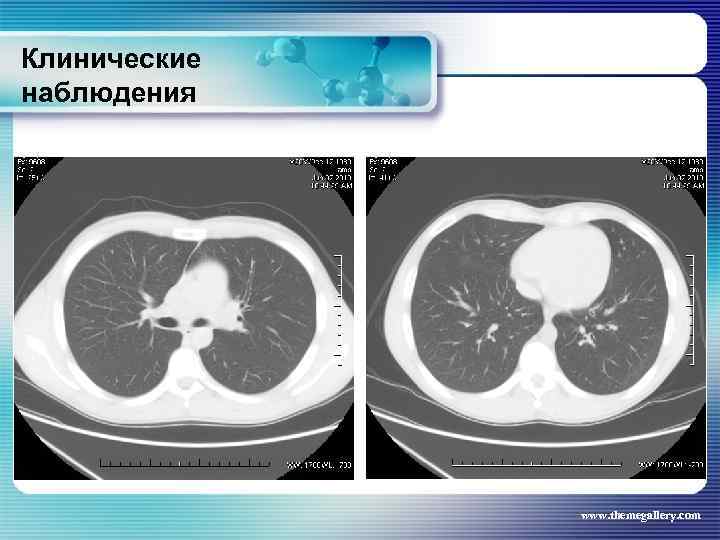

Клинические наблюдения Тот же пациент В мае 2010 года констатирована парциальная ремиссия. Для достижения полной ремиссии больному была выполнена ПХТ с аутотрансплантацией периферических стволовых клеток крови. Достигнута полная ремиссия к июню 2010 www. themegallery. com

Клинические наблюдения Тот же пациент В мае 2010 года констатирована парциальная ремиссия. Для достижения полной ремиссии больному была выполнена ПХТ с аутотрансплантацией периферических стволовых клеток крови. Достигнута полная ремиссия к июню 2010 www. themegallery. com